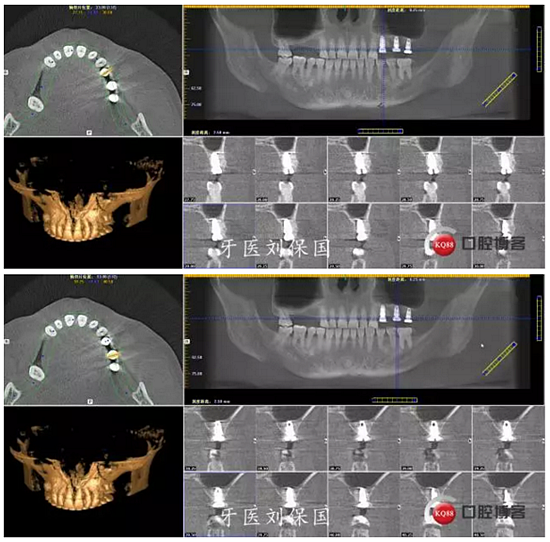

1.術前CT:

3.術后CT: